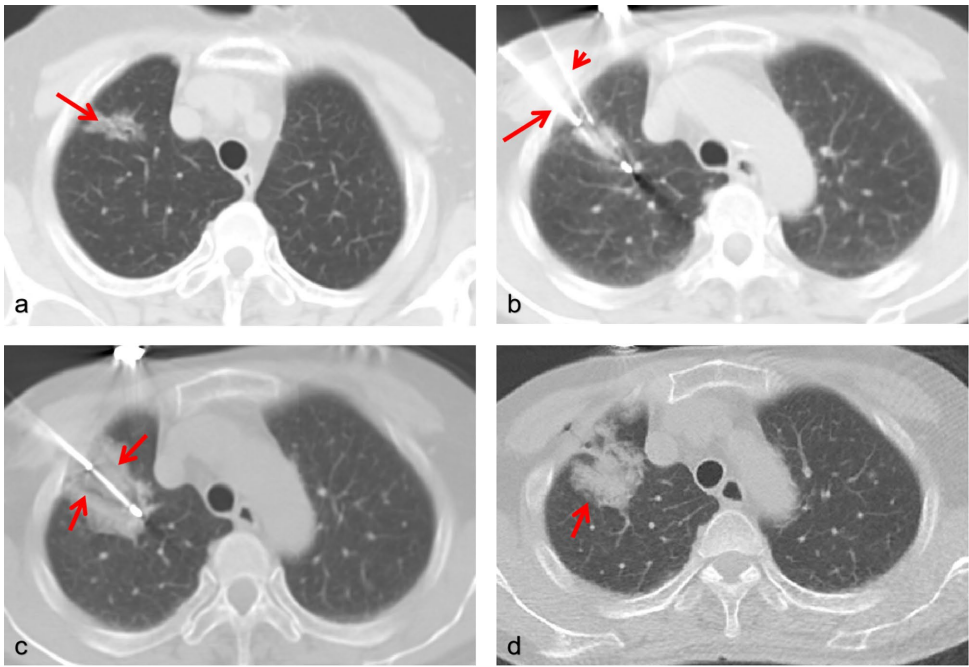

研究纳入124例高度可疑恶性肺结节患者(131个结节),分为同步组(Group A,38例/40结节)和分步组(Group B,86例/91结节)。采用16排CT引导,同步组通过同轴穿刺系统完成18G/20G活检后立即插入冷冻探针,实施2-3个冻融循环(每次10-15分钟冷冻+5分钟复温)。主要评估技术成功率、并发症(气胸、咯血等)及随访11.8个月(95%CI 10.2-13.4)的局部控制率。

未来需扩大样本量验证长期生存获益,并探索冷冻消融诱导的免疫效应(如PD-L1表达变化)与系统治疗的协同机制。研究创新性在于首次建立同步操作的标准化流程(见图2-3),为肺结节精准诊疗提供新范式。